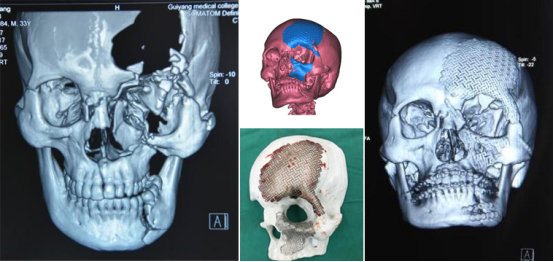

1、复杂牙、多生牙及各种埋伏智齿微创拔除。牙槽外科、口腔颌面创伤及口腔颌面部肿瘤的诊断及治疗,显微外科及颌面部软硬组织缺损的数字化修复重建。

3、口腔颌面创伤和骨折的诊断和序列治疗。

5、口腔颌面部显微外科和颌面部软硬组织缺损的数字化修复重建。